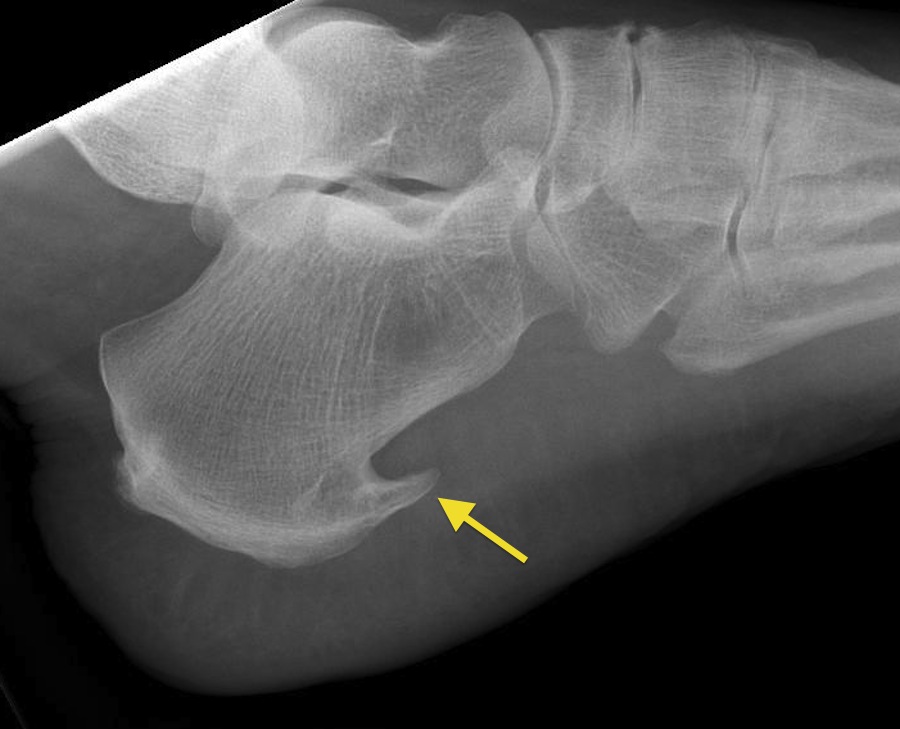

Speroni calcaneari

- Descrizione: Crescita anomala di un'appendice ossea nella faccia inferiore del calcagno (osso del Tallone). Causa molto Dolore.